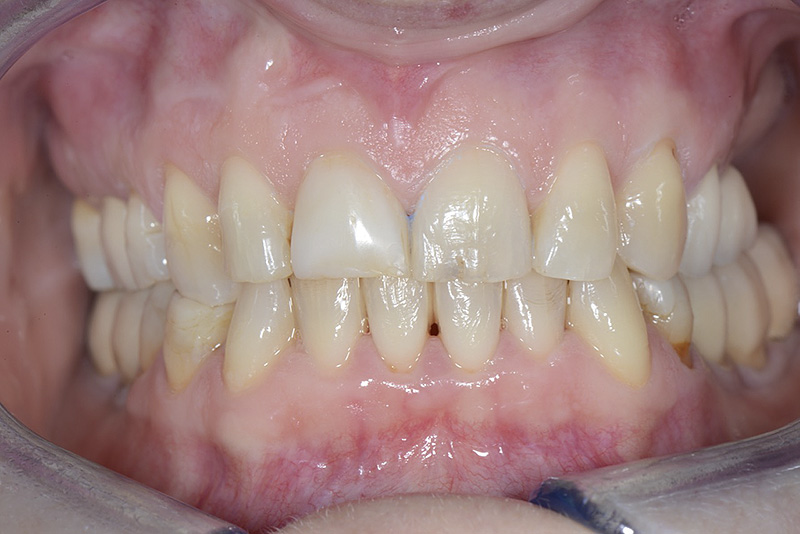

PREMESSA: in seguito all’estrazione dell’incisivo laterale superiore di destra, resasi necessaria per cause batteriche, si decide di affrontare il caso con il posizionamento di un impianto in sostituzione dell’elemento mancante dopo guarigione del sito infetto. Con tecniche rigenerative sia dei tessuti ossei mancanti a causa dell’infezione pregressa, sia dei tessuti gengivali che appaiono inizialmente troppo spostati in alto, si ripristina una corretta morfologia delle parabole (contorni) gengivali e delle papille interdentali (triangoli di gengiva tra due denti vicini).

Vengono utilizzati 2 tipi di provvisori: il primo, cementato ai denti vicini, viene utilizzato dal momento dell’estrazione del dente fino ad impianto osteointegrato (circa 6 mesi); il secondo, avvitato direttamente all’impianto, ha una funzione di prova estetica ma soprattutto di guida per la maturazione dei tessuti gengivali peri-implantari portandoli verso la maturazione completa prima di posizionare la corona finale in disilicato di litio.